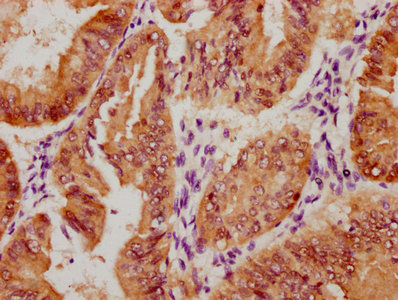

圖片:

The image on the left is immunohistochemistry of paraffin-embedded Human breast cancer tissue using CSB-PA969280(IRS2 Antibody) at dilution 1/100, on the right is treated with synthetic peptide. (Original magnification: ×200)